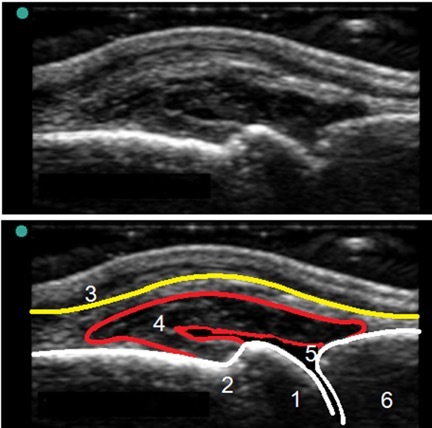

1. Distal Metacarpal

2. Metacarpal Notch

3. Extensor Tendon

4. Synovial Membrane

5. Dorsal Recess

6. Proximal Phalanx